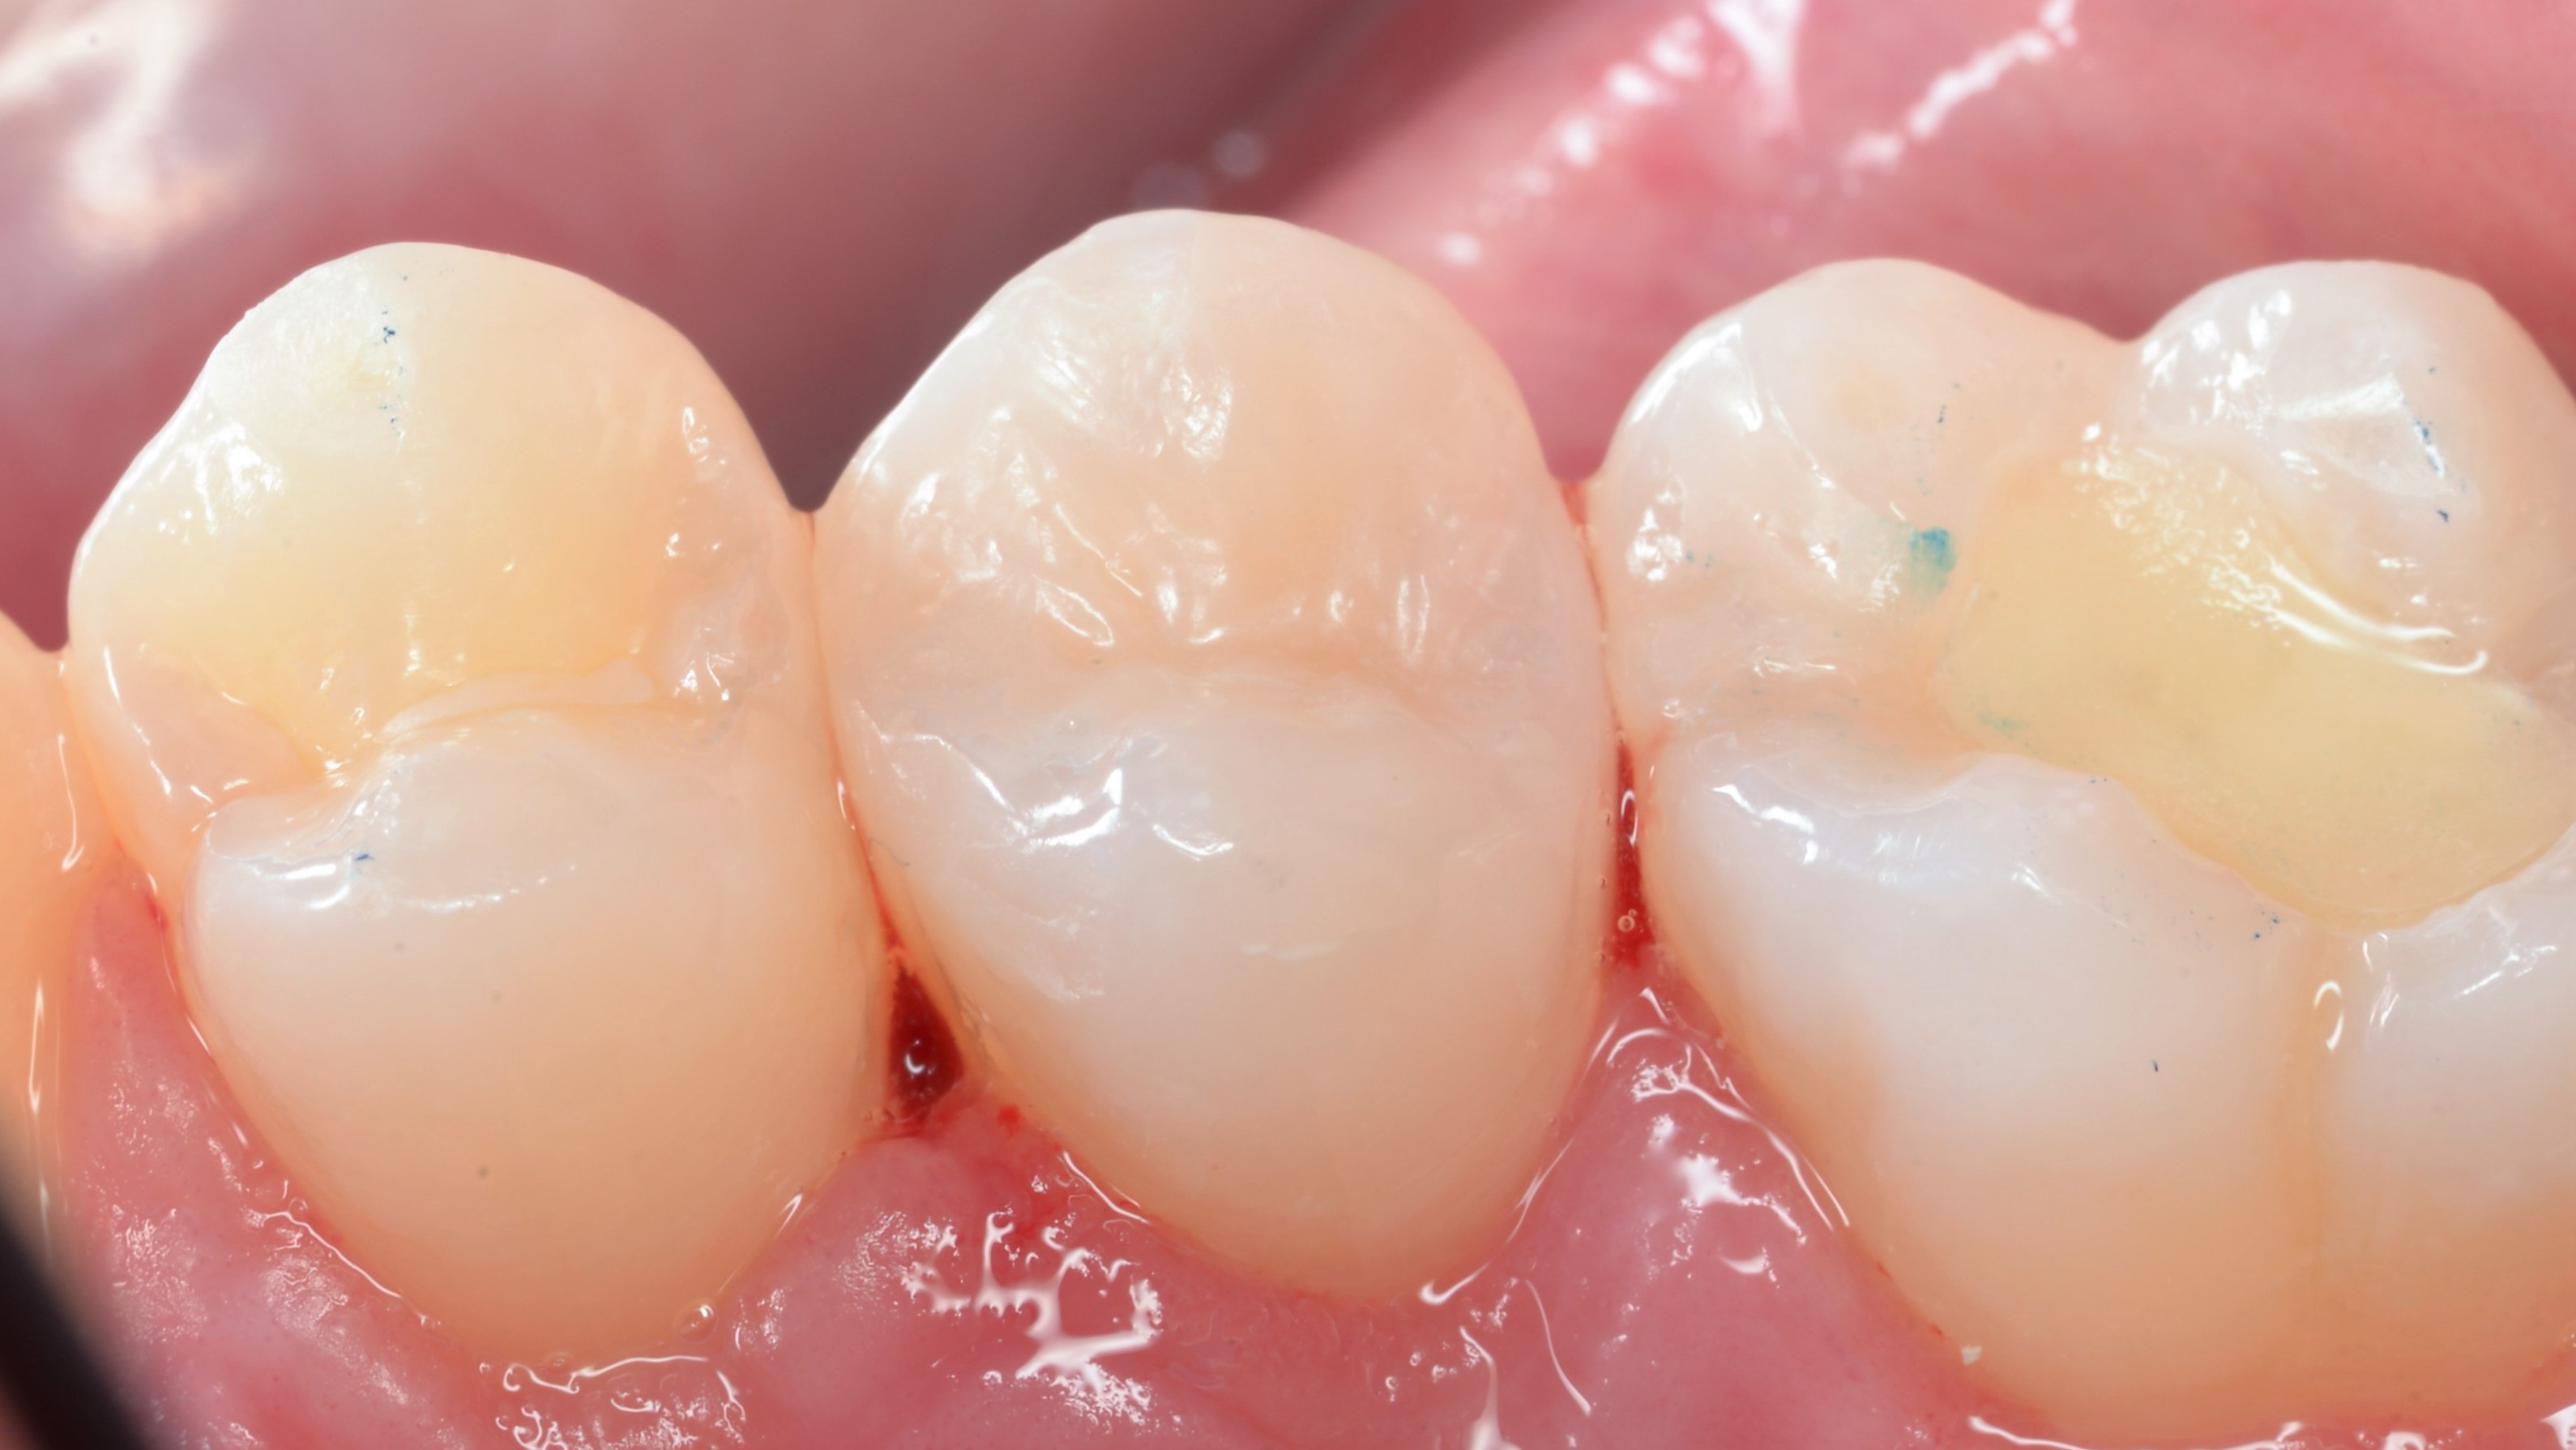

Wypełnienia wykończono dyskami ściernymi z nasypem z tlenku glinu (Sof-lex, 3M) oraz gumką impregnowaną węglikiem krzemu (BAL109F "brownie", Nevadent). Wstępne polerowanie wykonano gumkami diamentowymi Clearfil Twist DIA (Kuraray Noritake) oraz szczoteczkami nylonowymi (ryc. 9, 10). Odbudowy dostosowano w zgryzie i ostatecznie wypolerowano (ryc. 11, 12).

Ryc. 9. Wykończenie wypełnień (Sof-lex, 3M, BAL109F "brownie", Nevadent) i polerowanie wstępne (Clearfil Twist DIA, Kuraray Noritake, szczotka nylonowa).

Ryc. 10. Wykończenie wypełnień (Sof-lex, 3M, BAL109F "brownie", Nevadent) i polerowanie wstępne (Clearfil Twist DIA, Kuraray Noritake, szczotka nylonowa).

Ryc. 11. Stan po korekcie w okluzji i polerowaniu ostatecznym (Clearfil Twist DIA, Kuraray Noritake, szczotka nylonowa).

Ryc. 12. Stan po korekcie w okluzji i polerowaniu ostatecznym (Clearfil Twist DIA, Kuraray Noritake, szczotka nylonowa).